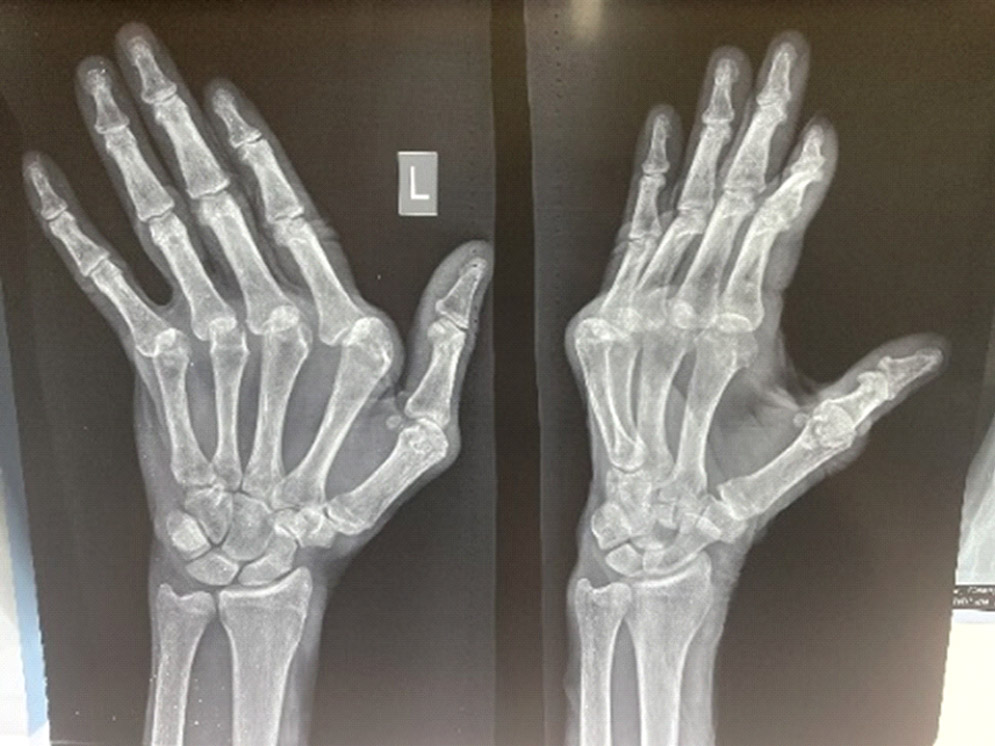

Рентгенологическая стадия поражения запястья определялась по классификации Larsen 1977 г. [12], которая в зависимости от степени сужения суставных щелей и выраженности костной деструкции включает пять стадий поражения суставов запястья. Согласно классификации Larsen, пациенты распределились следующим образом: у 8,7% была II стадия поражения суставов запястья, у 31,9% – III стадия, у 42,0% – IV стадия, у 17,4% – V стадия (рисунки 1–3).

Рисунок 2. Рентгенологическая картина поражения суставов запястья умеренной выраженности (Larsen 3-4 ст.).

Figure 2. X-ray pattern of moderate stages of wrist deformities (Larsen III-IV stages).